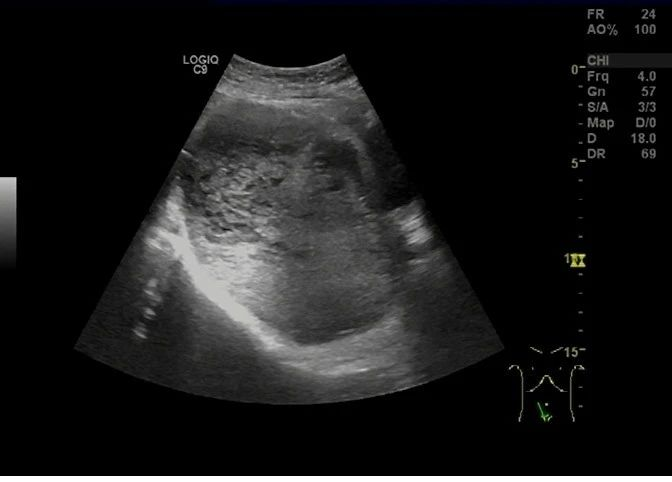

超声于右侧附件区见一囊实性团块,大小约 138 × 98 × 77 mm ,边界清,形态规则,内部回声不均,以实性为主(图 5), CDFI 于实性部分见少许血流信号(图 6), PW 测及低阻动脉血流频谱, RI:0.30 (图 7)。

图 5 右侧附件区见一囊实性团块,大小约 138 × 98 × 77 mm ,边界清,形态规则,内部回声不均